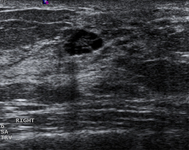

Ultrasonographic image of a simple cyst

Courtesy of Dr Lane Roland, University of Louisville; used with permission